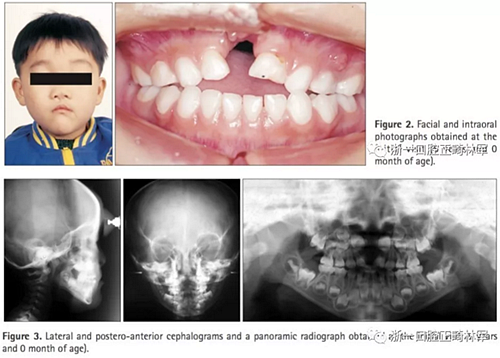

臨床檢查及診斷(圖2,3;表1):

患者表現為面中結構過寬;口內檢查提示前牙開合(覆合-2.5mm)及上牙弓窄縮。全景X線片顯示先天性缺失上頜乳中切牙及恒中切牙,前頜骨骨缺損和上頜左側乳切牙的萌發(fā)。頭側提示上下頜骨后縮(SNA,76.3°;SNB,74.8°;A to N,−3.9mm; Pog to N,−10.0mm) ,ANB角正常(1.5°),下頜平面角大(FMA,31.5°),下頜角大(125.4°)。上頜乳側切牙及下頜乳中切牙舌傾(primary U2 to SN,89.7°;primary IMPA,75.6°)。